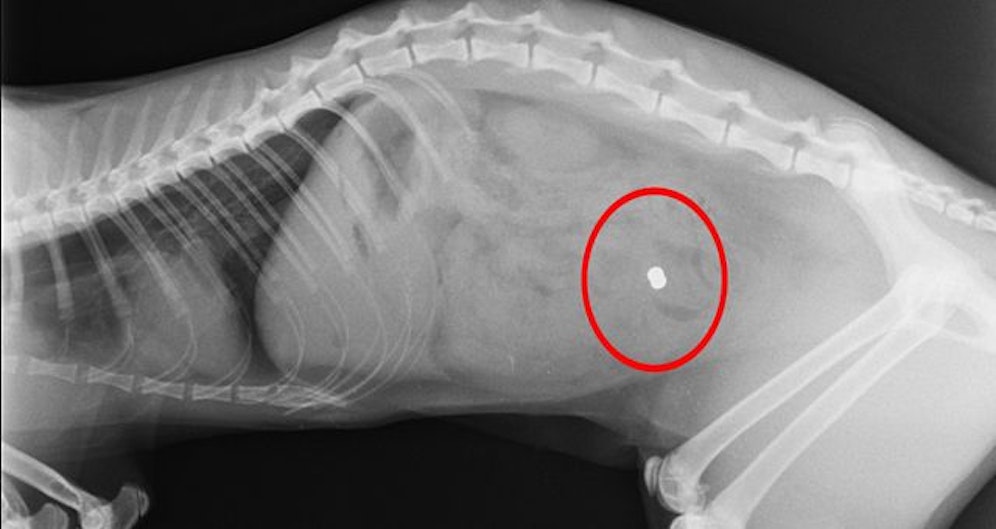

"Ein unbekannter Täter schoss mit einem Luftdruckgewehr bzw. einer Luftdruckpistole auf eine Katze, welche dadurch verletzt wurde", so die Polizei in einer Aussendung zu dem Fall.

Die Katze wurde zum Tierarzt gebracht. Dieser konnte das "Diabolo-Projektil" entfernen.